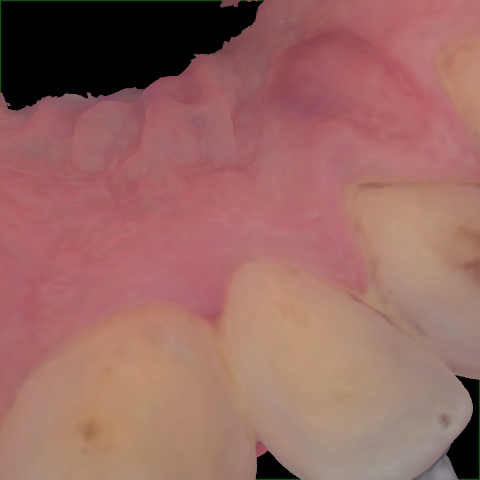

Image 1997 / 2000

NHD39969

Annotated as "Good"

Original Image Rendering Image